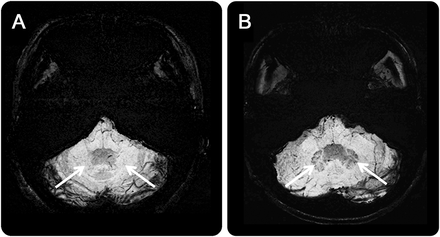

(A) Susceptibility-weighted图像(瑞士)揭示铁的缺乏hypointensity信号齿状核的病人ataxia-telangiectasia(箭头)相比,一个年龄和sex-matched正常控制参与者(B),而齿状核信号与一个典型的黑铁相关存款是明显可见的瑞士(箭头)。